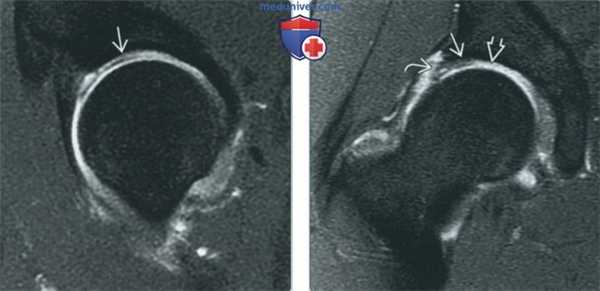

(Слева) МР-артрография в режиме Т1ВИ FS, косоаксиальный срез: в суставной тубе визуализируется скопление жидкости с неровным контуром, свидетельствующее о разрыве губы. Сравните с интактной задней суставной губой.

(Справа) МР-артрография в режиме Т1ВИ FS, сагиттальный срез, этот же пациент: наблюдается, что разрыв распространяется от периферии к основанию суставной тубы, что позволяет отнести его к радиальному типу. (Слева) МР-артрография в режиме PD FS, сагиттальный срез: визуализируется комплексный де генеративный разрыв передневерхней суставной тубы. Достаточно часто такие разрывы протекает бессимптомно.

(Справа) МР-артрография в режиме Т1ВИ FS, коронарный срез: жидкость разделяет верхнюю губу на два листка с зубчатыми краями, что характерно для дегенерации и разрыва. (Слева) МР-артрография в режиме PD FS, сагиттальный срез: выявляются разрыв задней суставной губы и паралабральная киста. Разрывы в этой области встречаются редко и обычно возникают в результате заднего подвывиха или вывиха. Также наблюдается разрыв передней суставной губы.

(Справа) МР-артрография в режиме PD FS, косоаксиальный срез, этот же пациент: подтверждается наличие разрыва и кисты.